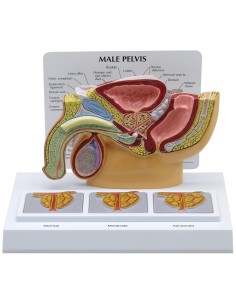

Scopri il Mondo dell’Anatomia con Modelli anatomici di Precisione

Modelli Anatomici Dettagliati per Ogni Necessità

Dal cranio in 22 parti con incastri magnetici ai modelli di colonna vertebrale, da quelli di articolazioni a quelli di cuore, ogni pezzo della nostra collezione è progettato per un’immersione totale nello studio dell’anatomia umana. I nostri modelli, realizzati tramite scansioni di ossa vere, garantiscono un’esperienza tattile autentica e una fedeltà di peso quasi identica agli originali.

Strumenti Didattici Innovativi per l’Educazione e la Pratica Medica

Essenziali per studenti e professionisti, i nostri modelli anatomici sono strumenti didattici che permettono di osservare le strutture anatomiche con precisione, eliminando la necessità di dissezioni o studi invasivi. Sono inoltre utili per spiegare ai pazienti le patologie, rendendo la comunicazione più efficace e risparmiando tempo prezioso.